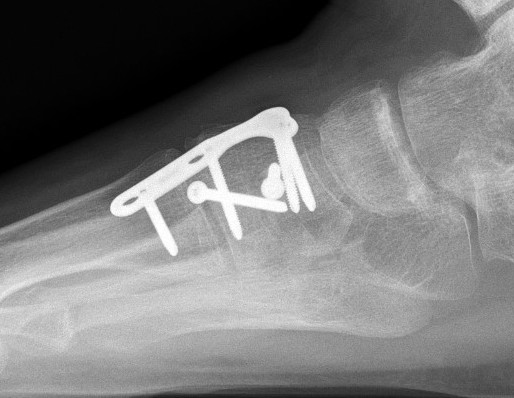

Primary Arthrodesis